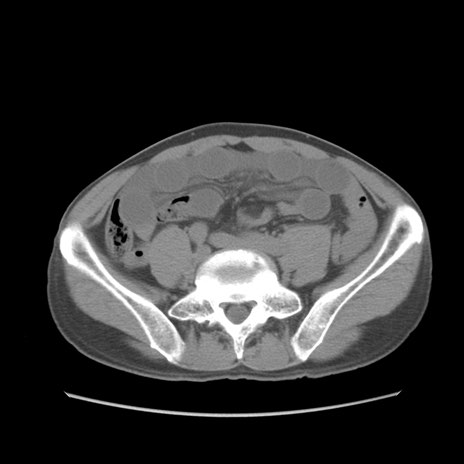

症例56 CT(横断像)

脂肪ウインドウ